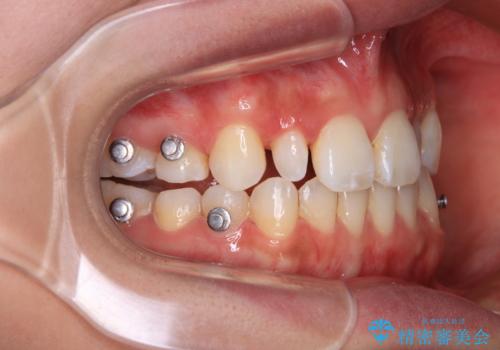

飛び出した前歯 インビザラインを用いた抜歯矯正治療

- 前方に飛び出した前歯を気にして来院された患者様です。

遠方の地元へ転居する予定があるとのことで、インビザラインによる治療を希望されていらっしゃいました。

上下前歯同士の距離が離れているため、上顎左右第一小臼歯2本を抜歯することで前突を改善することとしました。

しかしながら、左右ともに側切歯が矮小歯であるため、矯正治療で矮小歯前後にスペースを作り、矯正治療後にオールセラミッククラウンにて補綴治療を行うこととしました。

治療途中で地元へ転居され、飛行機での通院となったため、治療期間が長くなりましたが、自然で整った口元に仕上げることができました。